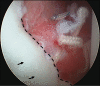

Glenoid articular cartilage lesion is a rare complication following traumatic anterior dislocation of the shoulder. We report the case of a 14-year-old male rugby player with traumatic anterior shoulder instability, an extensively flapped lesion on the glenoid articular cartilage, and an osseous Bankart lesion. Arthroscopic findings revealed that the glenoid cartilage was flap-detached, extending from the anteroinferior to the center. Repair of the osseous Bankart lesion using suture anchors and resection of the unstable peripheral part of the cartilage was performed arthroscopically. The main region of the injured articular surface was left untouched. During postoperative follow-up, absorption of the glenoid articular surface near the suture anchor holes was identified. Arthroscopic examination three months post-surgery showed that the flap detached lesion of the residual cartilage was stable and appeared adapted on the glenoid surface. The resected area was covered by fibrous tissue. A follow-up computed tomography scan revealed that the osseous lesion was united. The patient returned to his previous sports capacity eight months following the operation. At the 2-year-follow-up, magnetic resonance imaging revealed that the glenoid surface was remodeled to a flattened round shape with no signs of osteoarthritis, exhibiting proper conformity of the joint surfaces to the humeral head. Arthroscopic Bankart repair using suture anchors may cause bone resorption at the glenoid surface, leading to remodeling of the glenoid surface from the damaged glenoid cartilage lesion in young patients.